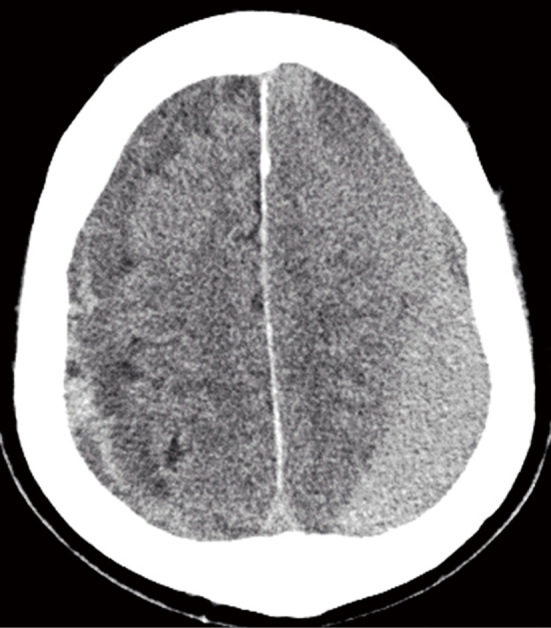

Bilateral chronic subdural hematoma is treated by burr-hole surgery. Patients may undergo simultaneous bilateral surgery, or unilateral surgery which occasionally necessitates subsequent contralateral surgery due to the contralateral chronic subdural hematoma progression. Contralateral chronic subdural hematoma progression is not well understood, and an optimal surgical strategy for bilateral chronic subdural hematoma remains undefined. This study aimed to identify predictors for contralateral chronic subdural hematoma progression following unilateral surgery in patients with bilateral chronic subdural hematoma, specifically examining contralateral chronic subdural hematoma presented as membranous (indicating an older hematoma) and the contralateral hematoma volume. In this prospective observational study, 39 patients with bilateral chronic subdural hematoma requiring surgery were included between February 2020 and July 2024. All patients initially underwent unilateral burr-hole surgery. Additional surgery was performed if contralateral chronic subdural hematoma progression occurred. The preoperative predictors of contralateral chronic subdural hematoma progression were investigated. Among the 39 patients, 16 (41%) experienced contralateral chronic subdural hematoma progression, necessitating contralateral surgery. Of the 12 patients with membranous-type chronic subdural hematoma on the contralateral side, contralateral chronic subdural hematoma progression developed in one patient (8%), whereas 15 (56%) of the 27 patients with non-membranous type had contralateral chronic subdural hematoma progression. Logistic regression analyses revealed that membranous-type hematoma was negatively associated with the risk of contralateral chronic subdural hematoma progression, with an odds ratio of 0.07 (95% confidence interval: 0.01-0.65). Additionally, preoperative hematoma volume on the contralateral side was identified as a risk factor for contralateral chronic subdural hematoma progression, with an odds ratio of 1.58 (95% confidence interval: 1.04-2.40) per 10 mL increase. The membranous type and small volume of contralateral chronic subdural hematoma were associated with a lower risk of contralateral chronic subdural hematoma progression after unilateral surgery in bilateral chronic subdural hematoma. We suggest applying unilateral surgery selectively to bilateral chronic subdural hematoma with these characteristics.

Abstract Image